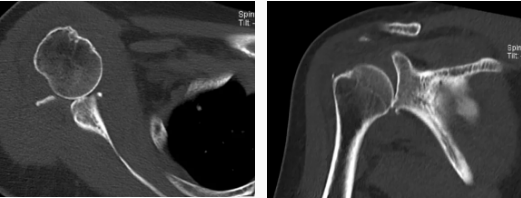

病例2

病史摘要:女性,65歲,跌傷致右肩活動(dòng)受限9天。

CT圖示:右側(cè)肱骨頭后上部局部明顯凹陷,局部骨皮質(zhì)欠光整(箭頭),外緣見(jiàn)小片狀骨碎片影;右側(cè)肱骨頭向下方移位,關(guān)節(jié)間隙增寬;前下盂唇骨質(zhì)不連續(xù),見(jiàn)多發(fā)小碎骨片影并游離(三角形)。